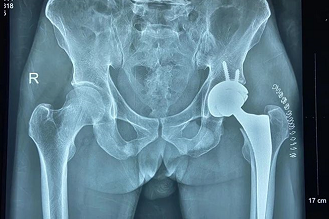

股骨颈骨折(左图)和股骨粗隆间骨折(右图)

老年髋部骨折的典型术式——髋关节置换

半髋关节置换

全髋关节置换

创伤科主任李培龙表示:至于选择哪种手术方式,则一般遵循以下基本原则:对于股骨粗隆间、粗隆下骨折一般首选采用内固定方式;股骨颈骨折55岁以下选择内固定,而对于年龄大于55岁以上的股骨颈骨折,多选择半髋关节置换或全髋关节置换。当然,这只是一般情况,具体手术方案必需要考虑的要素是患者现在的“生理情况”,而非患者的年龄,即要做到“个体化治疗”。